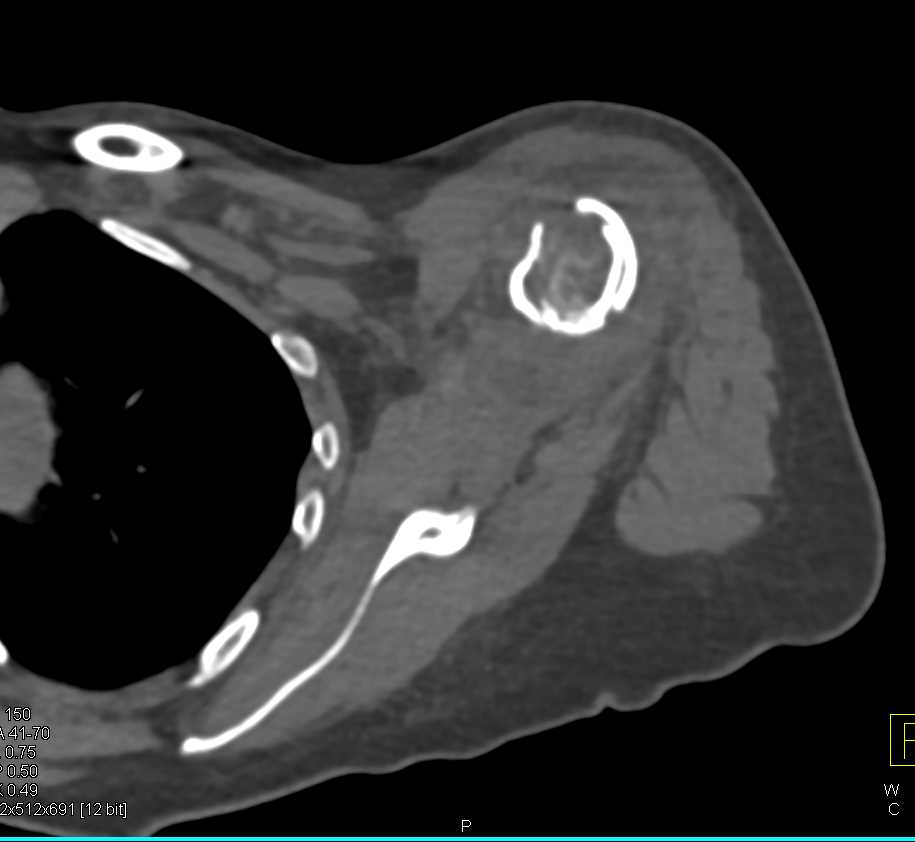

Fracture Neck of the Humerus